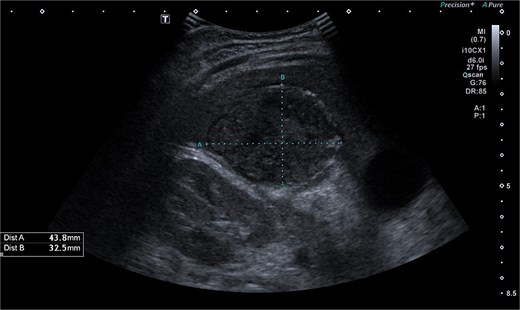

Imaging plays a crucial role in diagnosing appendicitis and its complications. Ultrasound is often the initial modality used, but it may have limited sensitivity in detecting intra-abdominal abscesses, particularly when the appendix is not visualized or when findings are inconclusive [4, 5]. In such cases, contrast-enhanced CT is considered the gold standard, providing detailed visualization of the appendix and associated complications, including abscess formation [2, 4]. In the present case, the initial ultrasound findings suggested an atypical position of the appendix and a pathological fluid collection, but CT imaging confirmed a retrocecal appendix and subhepatic abscesses (Figs 4 and 5), guiding appropriate management.

CT axial view of a subhepatic abscess. Contrast-enhanced capsule and fluid-air level visible.